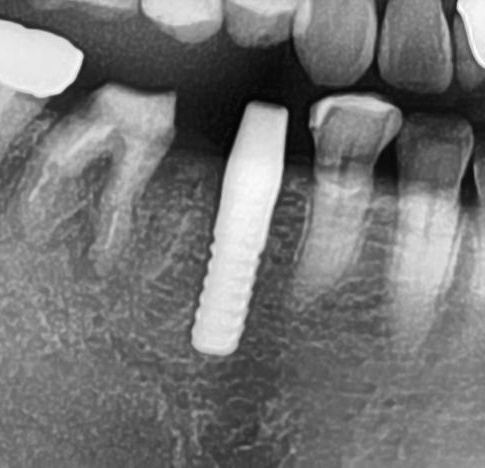

開けた穴に、専用道具を使ってネジを締めるように長さ2センチ程のインプラントを骨に埋め込んでいきます。

しっかりとインプラント埋め込まれた後は、動揺がないか、噛んだ時に当たらないかなどを確認して、最後にパノラマ写真を撮影して今回のオペは終了となりました。